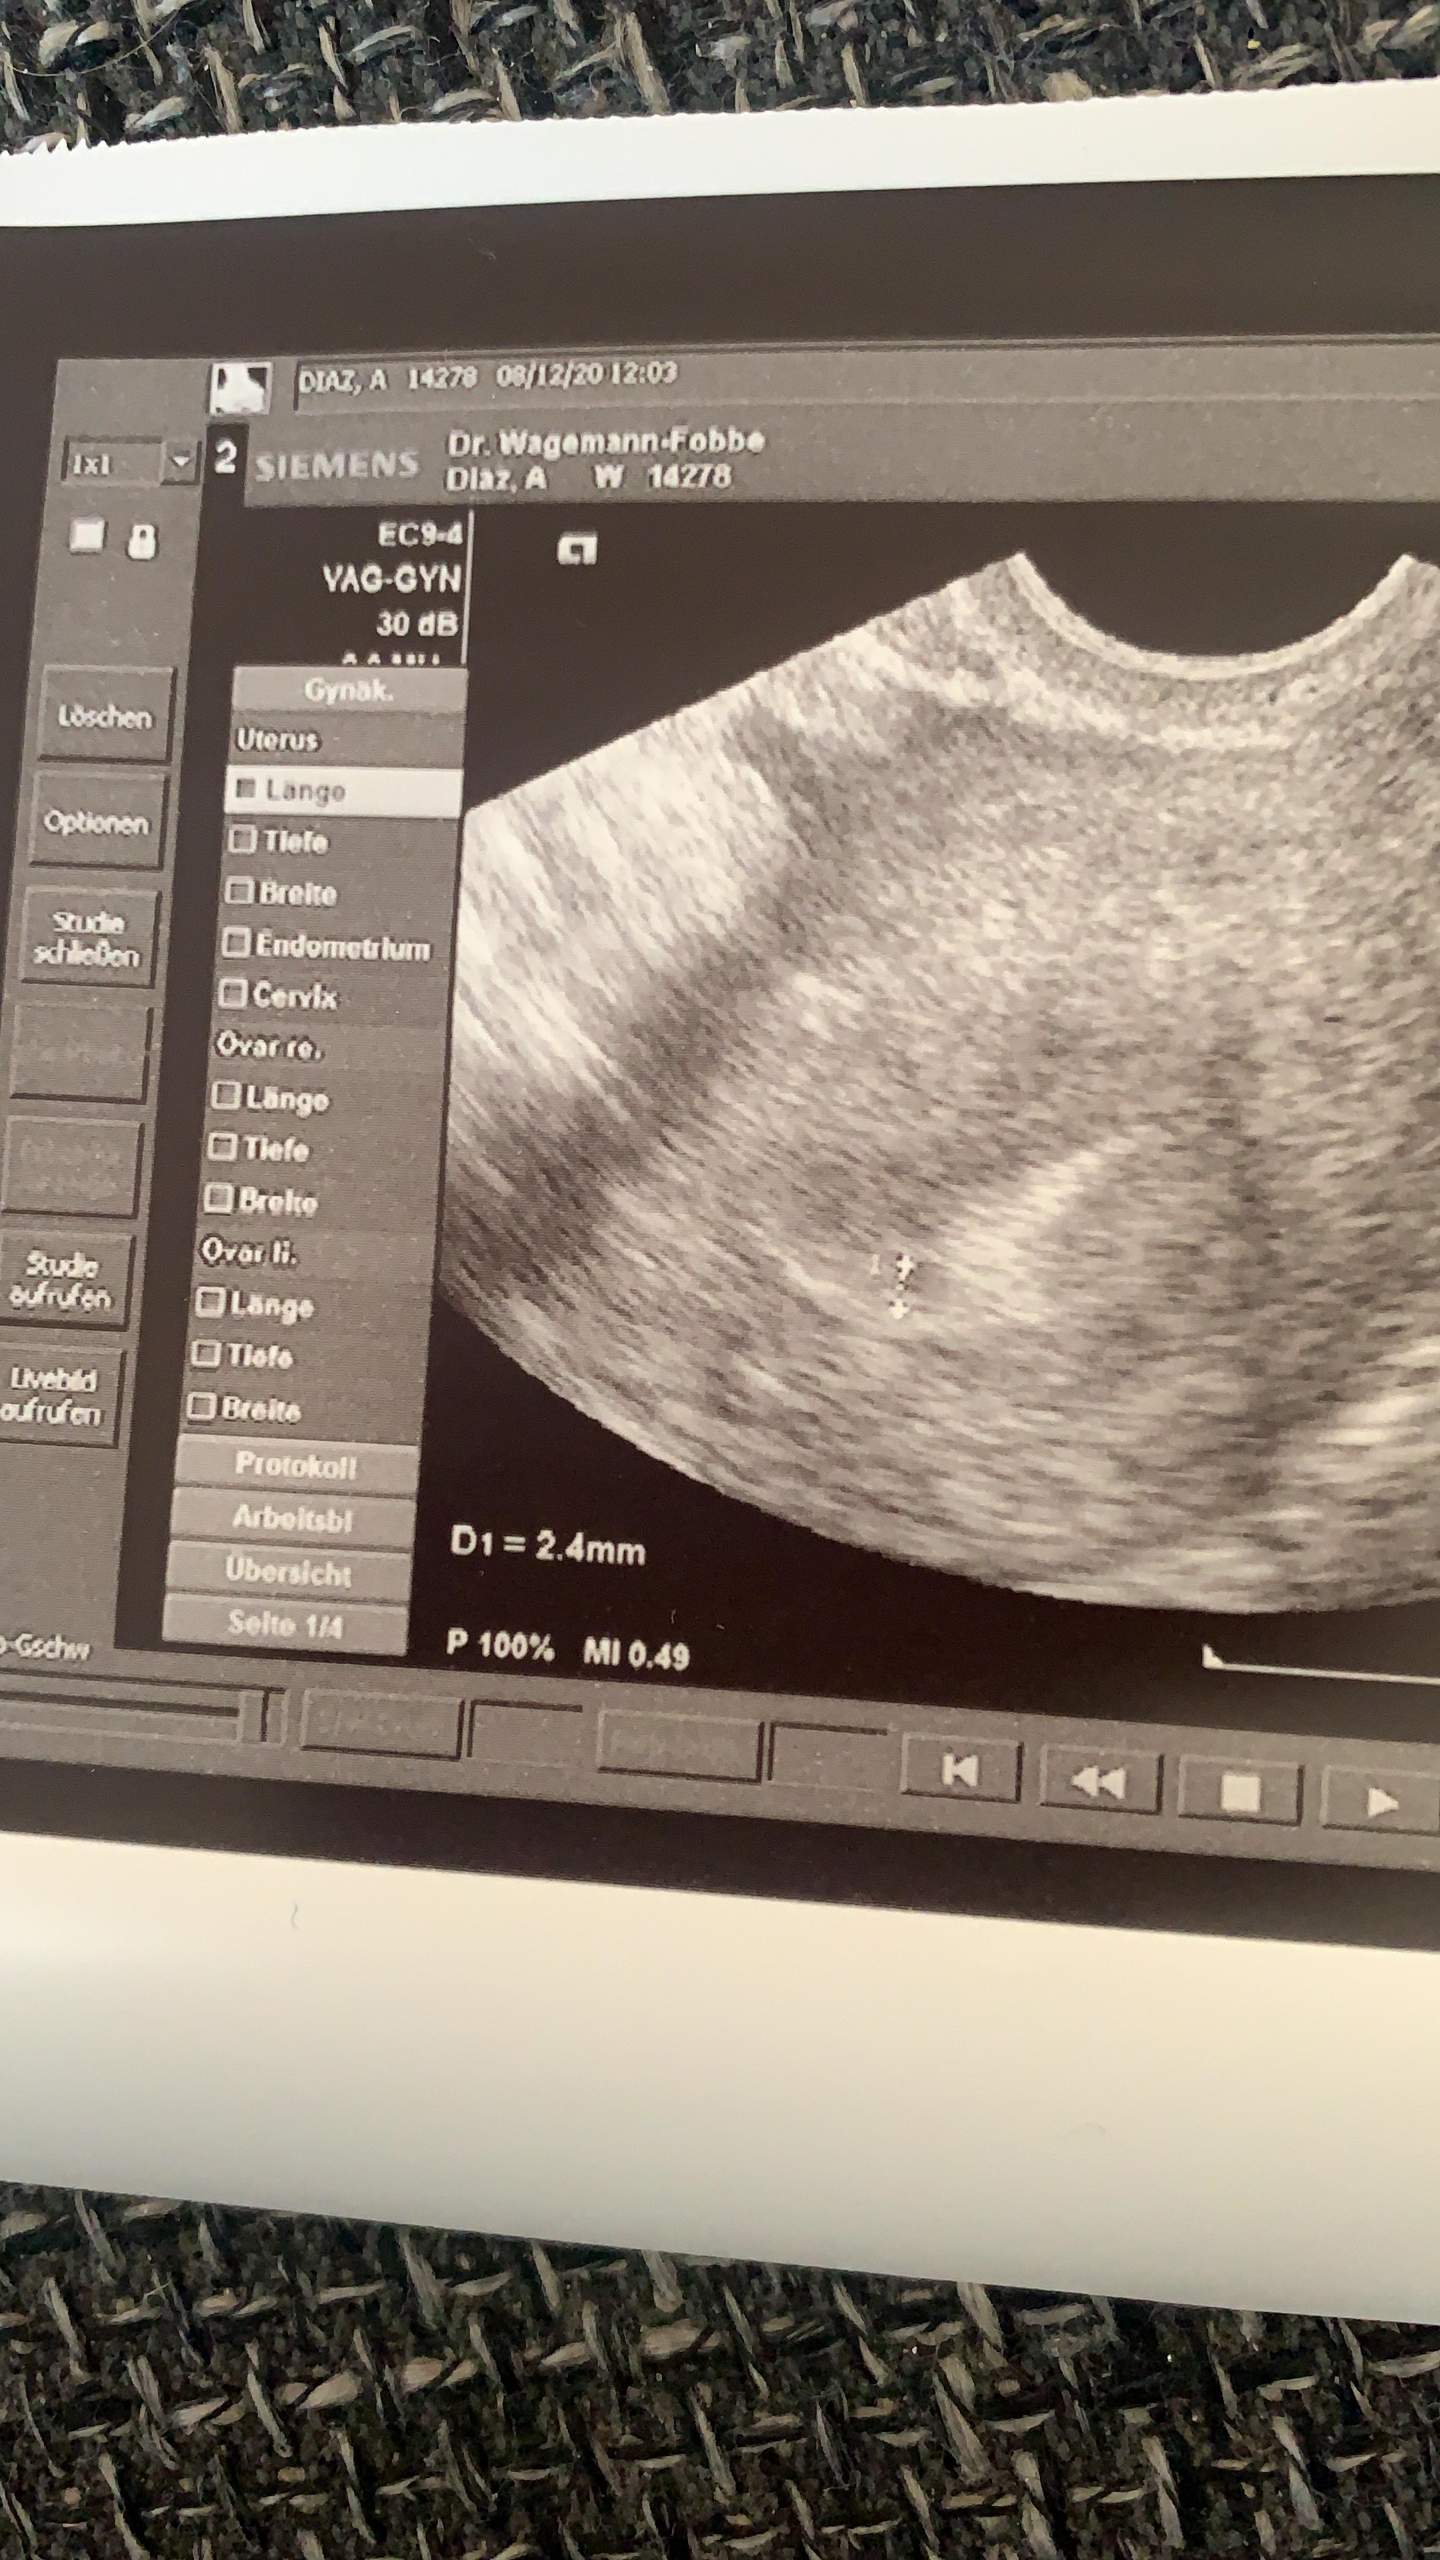

4+3 ssw ultraschall. War dann heut beim Gyn- es ist aber nix im US zu sehen. So klein das neue Leben noch sein mag es macht sich bei Ihnen unter Umständen bereits bemerkbar. SSW am 24092014 745 Uhr.

Ultraschall in der 4. Es schwimmt in einer winzigen Fruchtwasserhöhle die manchmal auch schon in der 5. Erster Ultraschall nichts zu sehen 46 Antwort von KatzeKira 25.

Die befruchtete Eizelle hat sich in Deiner Gebärmutter eingenistet. Ab diesem Zeitpunkt wird der kleine Embryo von Tag zu Tag immer größer werden. SSW einen Ultraschall-Termin hat der wird leider noch nichts besonderes sehen können.

Ihr Baby ist mit seinen drei Wochen so klein wie ein Samenkorn oder ein Brotkrümel etwa 2 mm. Ultraschall bei 53 erfahrungen. Hab am Sonntag einen Schwangerschaftstest gemacht-POSITIV.